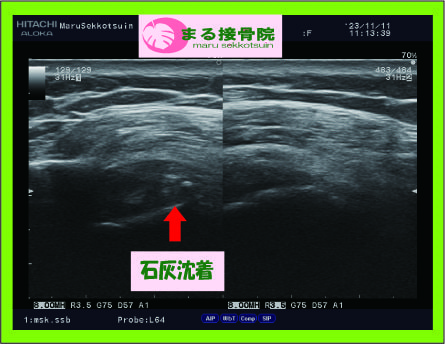

こういう、急な肩の痛みの場合、臨床的にとても多いのが、「石灰沈着性腱板炎」というものがあります。

石灰沈着性腱板炎.jpg

では、石灰沈着性腱板炎とはどのようなものでしょうか??

肩の筋肉内に沈着したリン酸カルシウム結晶(石灰)によって、原因不明で突然、炎症が生じて肩の痛みで動かせる範囲が狭くなる状態です。